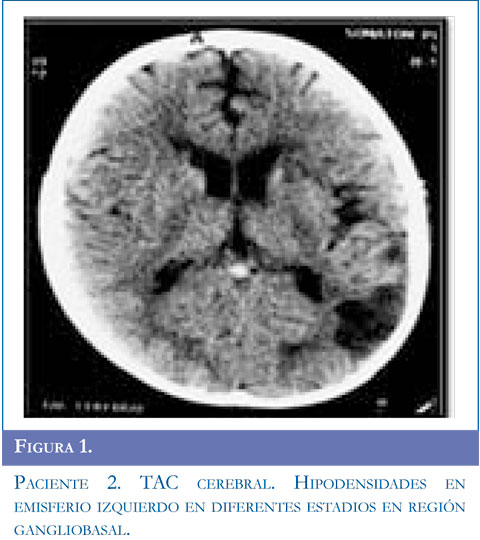

Ingresa al servicio de urgencias por presentar alteración de la marcha dado por disminución de la fuerza en hemicuerpo derecho y dificultad para el habla, acompañado de movimientos clónicos de miembro superior derecho, sin perdida de conciencia la mirada de 10 segundos de duración, se repiten en 5 oportunidades y ceden con benzodiacepinas. Se inició manejo anticonvulsivante. Al examen tenía parálisis facial derecha periférica, hemiparesia derecha con hiperreflexia músculotendinosa, disimetría, disdiadococinesia ipsilateral y afasia motora. Se realizó TAC simple de cráneo y contrastado con lesión gangliobasal izquierda de características isquémicas. Presentó clonias de brazo y aumento de la debilidad faciobraquial derecha, hemianopsia heterónima derecha, se realizó RMC con hipodensidad parieto temporal izquierda compatible con lesión isquémica en territorios de arteria cerebral media izquierda. Se inició enoxaparina1mg/k/dosis y calcio antagonista. El perfil hematológico fue normal. La panangiogra-fía evidenció enfermedad de Moyamoya estadio V de Suzuki. Valorado por neurocirugía se consideró manejo quirúrgico y el día 19 del cuadro clínico se realizó encefaloduroarteriosinangiosis. En la actualidad tiene afasia motora en mejoría, hemiparesia derecha y componente distónico ipsilateral, hiperre-flexia derecha, continúa manejo con fisiatría, terapia física, ocupacional y del lenguaje. Figuras 1,2 y 3.